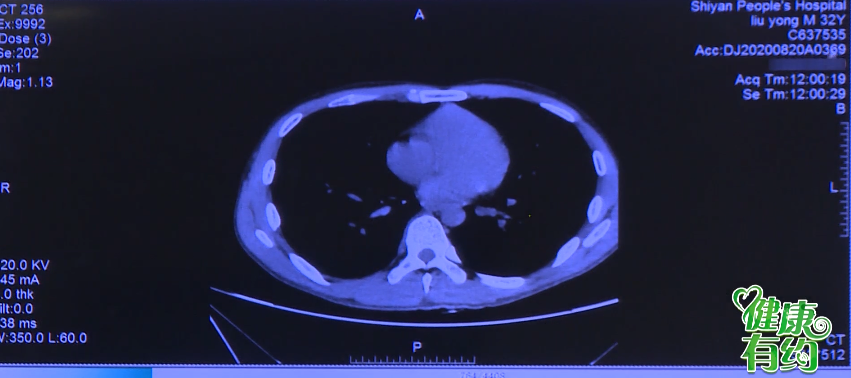

58岁男子不幸患上肝癌

十堰市人民医院专家组

为患者精准切除肿瘤